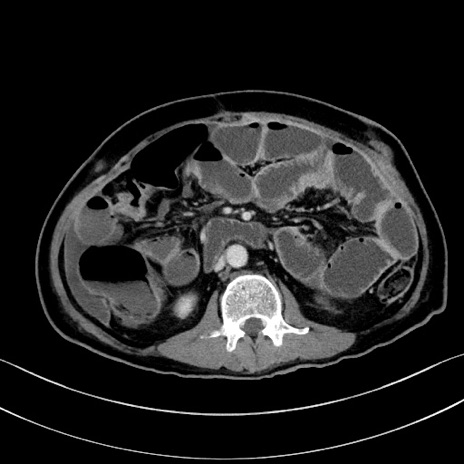

症例28(横断像)

【症例】60歳代男性

【主訴】嘔吐

【現病歴】胃癌にて胃全摘後。食思不振が悪化し、夜中に嘔吐することがある。

【既往歴】胃癌、胃全摘、脾摘、胆摘後

【データ】WBC 5900、CRP 10.56